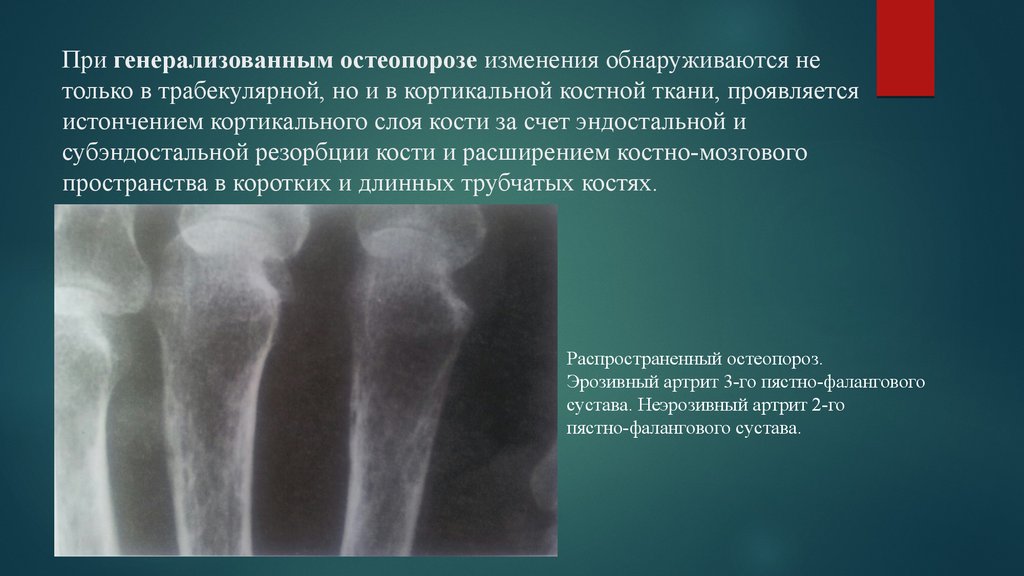

Рентгеновские снимки остеосклероза костной ткани